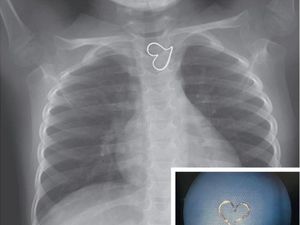

Tusuk gigi yang nyangkut di tenggorokan mengakibatkan infeksi hingga terjadi gagal jantung dan kematian. Tusuk gigi kerap luput dari pemeriksaan sinar X.